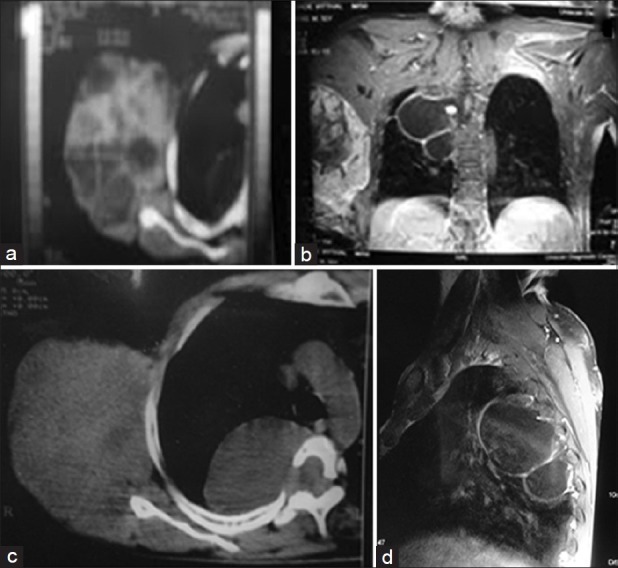

Malignant peripheral nerve sheath tumor (MPNST) is a malignant spindle cell tumor of the soft tissue thought to be derived from the components of nerve sheath. MPNSTs are mainly located in the buttocks, thighs, brachial plexus, and paraspinal region. The objective of this article is to describe a case of neurofibromatosis type 1 who developed neurofibrosarcoma of the right lateral thoracic nerve with thoracic meningoceles, a rare coincidental finding which has not yet been reported in the English medical literature, and how both the conditions were managed in the same sitting.